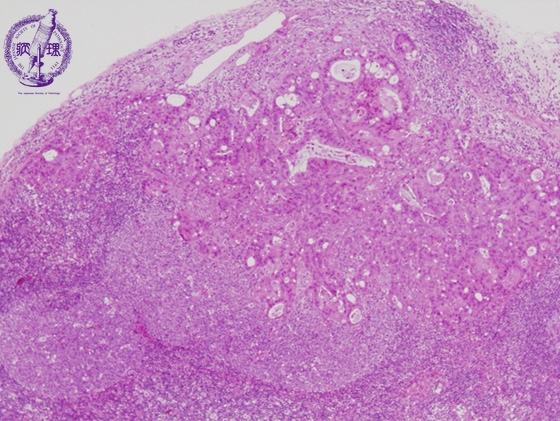

- ★(9)Cancer metastasis into the lymph nodes

Microscopic image (H&E low power view): Nests of gland-forming adenocarcinoma (colon cancer) are found in the subcapsular sinus (arrows). The lymph node follicular structure is relatively preserved and follicles are often rather large (arrow heads). In general, cancer metastasizes via the lymphatic system. Consequently, metastatic disease is typically first seen in the subcapsular sinus where the lymph fluid enters the lymph node.